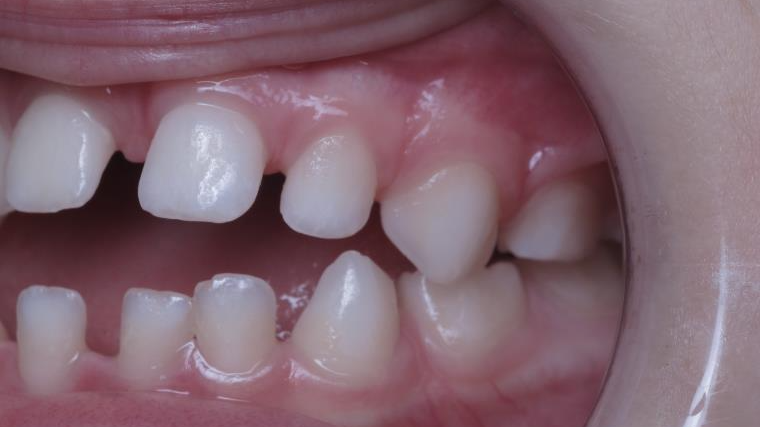

appareillage mobile pendant 3 ans

sectionnel multibagues pendant 8 mois

surveillance évolution de la dentition

bilan de début et en cours de traitement